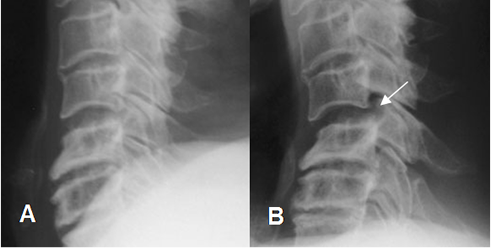

Las anormalidades en la alineación descritas incluyen: interrupción de las líneas intervertebrales anterior y posterior, de la línea espinolaminar, rotación de las apófisis espinosas, ensanchamiento de la distancia interespinosa e interpeduncular. (7, 39). (Fig 164, 165 y 166).

Fig 164. Desalineación.

Rx lateral. Anterolistesis post-traumática, con interrupción en las líneas intervertebral anterior y posterior.